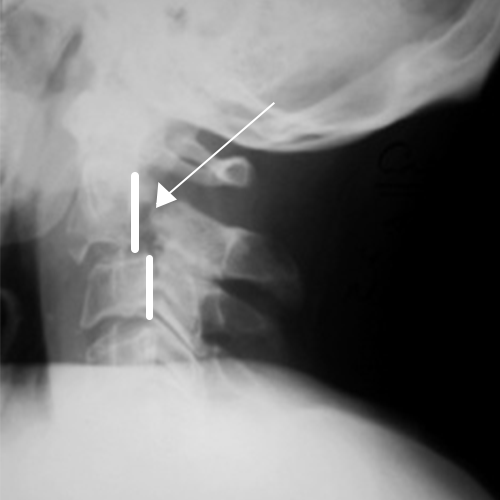

Рис.1 Перелом палача. Тело С2 смещено кпереди относительно С3 (спондилолистез). Стрелкой указан перелом ножки